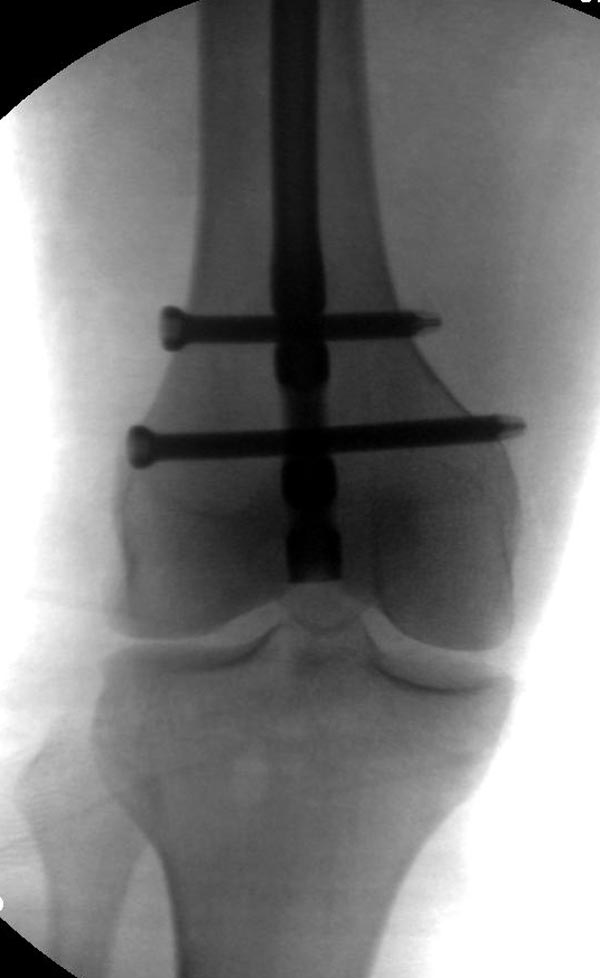

Здесь выставлен ренгенограммы больного, ему 21, травму получил в

результате высокоскоростной погони на украденной машине, которая

закончилась смертью трех остальных“боевых комрадов”. Начатую коллегой

открытую операцию на шейке пришлось закончить мне, установкой винтов и

ретроградной фиксацией бедра. Выписка в обычное сроки и наблюдался

амбулаторно. Каждый раз напоминали о возможности осложнений ввиде

несращения! По истечению 4 месяцев появились признаки варусной

деформации. На СТ срезах несращение шейки и бедра. Риминг, замена на

более толстый гвоздь и вальгусная остеотомия.